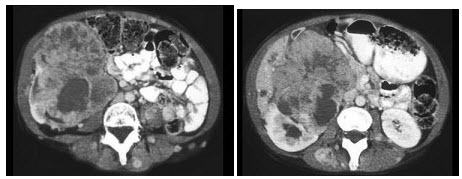

D.右侧胆脂瘤

如图所示,这两个时相提示()